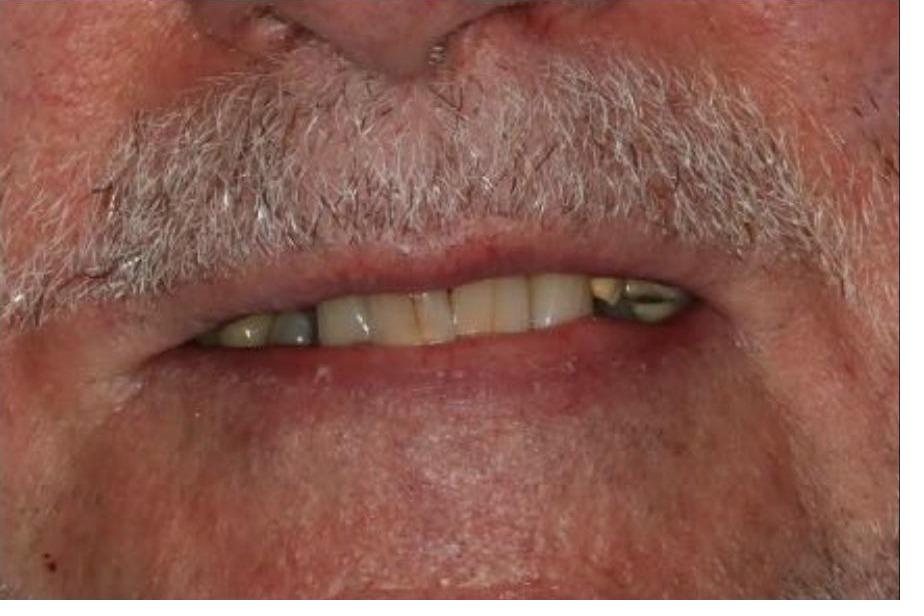

To improve this patient's dental health, esthetics and function, upper and lower implants were placed. I then fabricated an upper screw-retained implant bridge and a lower Overdenture, giving this patient back his smile and function. The patient was thrilled with the result and exclaimed "It looks good! I'll have all the women chasing me! I'd marry me if I wasn't already married!"

To improve this patient's dental health, esthetics and function, upper and lower implants were placed. I then fabricated an upper screw-retained implant bridge and a lower Overdenture, giving this patient back his smile and function. The patient was thrilled with the result and exclaimed "It looks good! I'll have all the women chasing me! I'd marry me if I wasn't already married!"

This patient was unhappy with his upper denture and lower partial denture with decayed lower teeth. Working with a periodontist and laboratory technician I fabricated a new upper denture and lower implant bridge with improved esthetics, dental health and function. He was extremely happy with the result.

Following restoration of this patient's cavities and periodontal health, implants were placed. I restored the implants with a screw-retained bridge adding gingival colored porcelain that was custom stained to match his soft tissue. The patient able to smile again with confidence, and extremely happy with the improvement in his dental health, function and esthetics.

This patient was unhappy with his upper denture and lower partial denture with decayed lower teeth. Working with a periodontist and laboratory technician I fabricated a new upper denture and lower implant bridge with improved esthetics, dental health and function. He was extremely happy with the result.